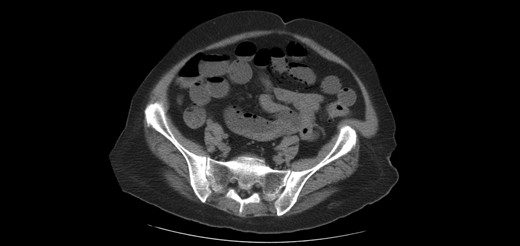

A 64-year-old female presented to the emergency department with a chief complaint of epigastric pain and nausea lasting 24 h. Relevant medical history includes congestive heart failure, interstitial lung disease, chronic obstructive pulmonary disease and prior open cholecystectomy. Home medications included a course of methylprednisolone for acute exacerbation of lung disease. On exam, her abdomen was tender and distended. Labs showed leukocytosis with normal lactate level. Figures 1 and 2 show abdominal computed tomography (CT) without contrast, significant for small bowel obstruction with intramural small bowel pneumatosis and extensive portal venous gas (PVG) within the left hepatic lobe. Emergent laparotomy was performed for acute abdomen. Exploration of the abdominal viscera revealed no evidence of inflammation, necrosis or perforation. The patient continued to have pain after surgery. Upper endoscopy was performed, revealing a non-perforated gastric ulcer which was treated with medical management until the pain resolved.

Extensive portal venous gas noted in the left lobe of the liver during the first admission. Laparotomy was negative for bowel ischemia.